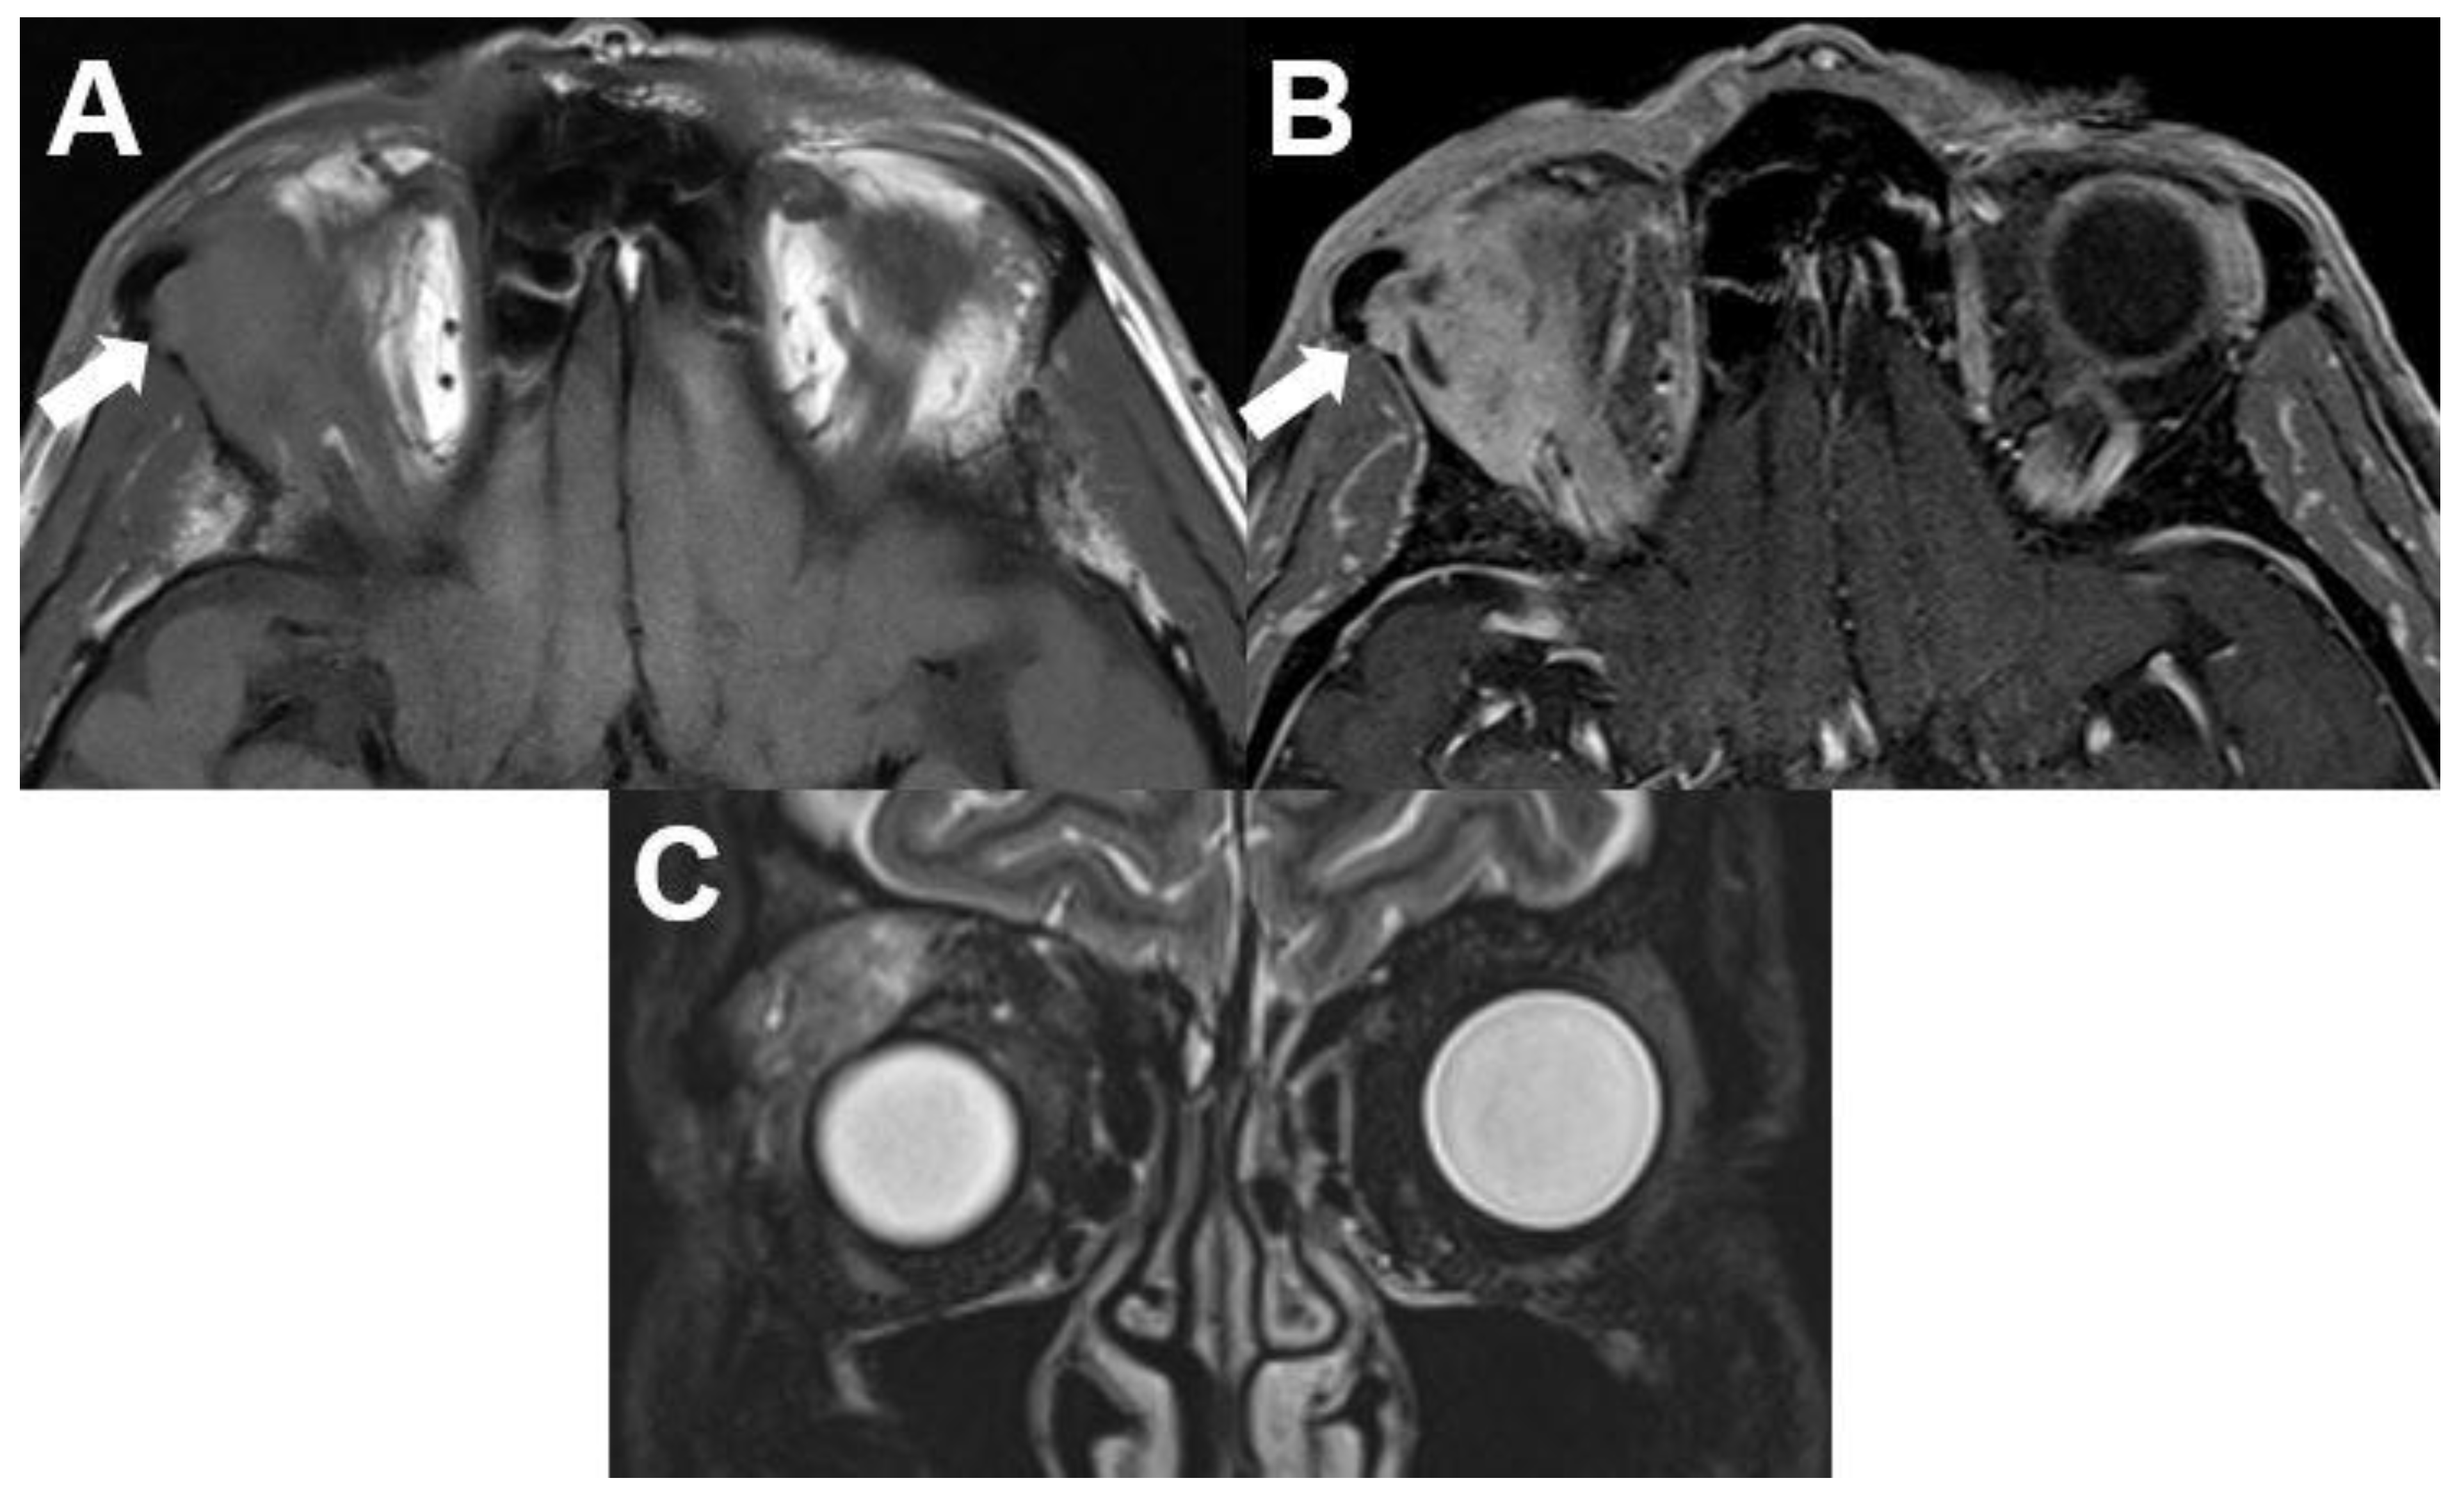

3.6.2. Rhabdomyosarcoma